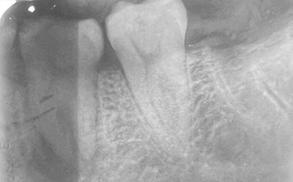

Paciente femenino de 26 años de edad, sin antecedentes médicos de importancia, la cual acude por odon tología asociado a segundo y tercer molar inferior izquierdo, asimismo nuevamente se realizó valoración integral por los servicios de próte sis bucal y endodoncia, quienes con sensan como mejor tratamiento la extracción dental. Nuevamente se propone realizar un TD del tercer molar inferior derecho. Realizamos estudios radiográficos de dicho órga no (Figura 8), extracción atraumáti ca del tercer molar inferior derecho para posterior trasplante al espacio del segundo molar inferior ipsila teral, finalizando con la colocación de una férula de alambre trenzado para mayor estabilidad por no tener un diente de apoyo posterior (Figu ra 9), se realiza mismo manejo anti biótico y analgésico. Actualmente se encuentra en seguimiento estrecho,

Octubre 2022 Figura 6. Fotografía oclusal de evolución posterior a 4 meses. Figura 7. Radiografía dentoalveolar de evolución posterior a 4 meses. Figura 8. Radiografía dentoalveolar inicial donde se observa caries de segundo grado en el segundo molar inferior derecho y tercer molar impactado. Figura 9. Radiografía dentoalveolar postoperatoria. Trasplante dental de terceros molares

Figura 10. Punto de sutura en cruz para estabilidad de tercer molar inferior izquierdo y férula de alambre trenzado. Figura 11. Radiografía dentoalveolar inicial.